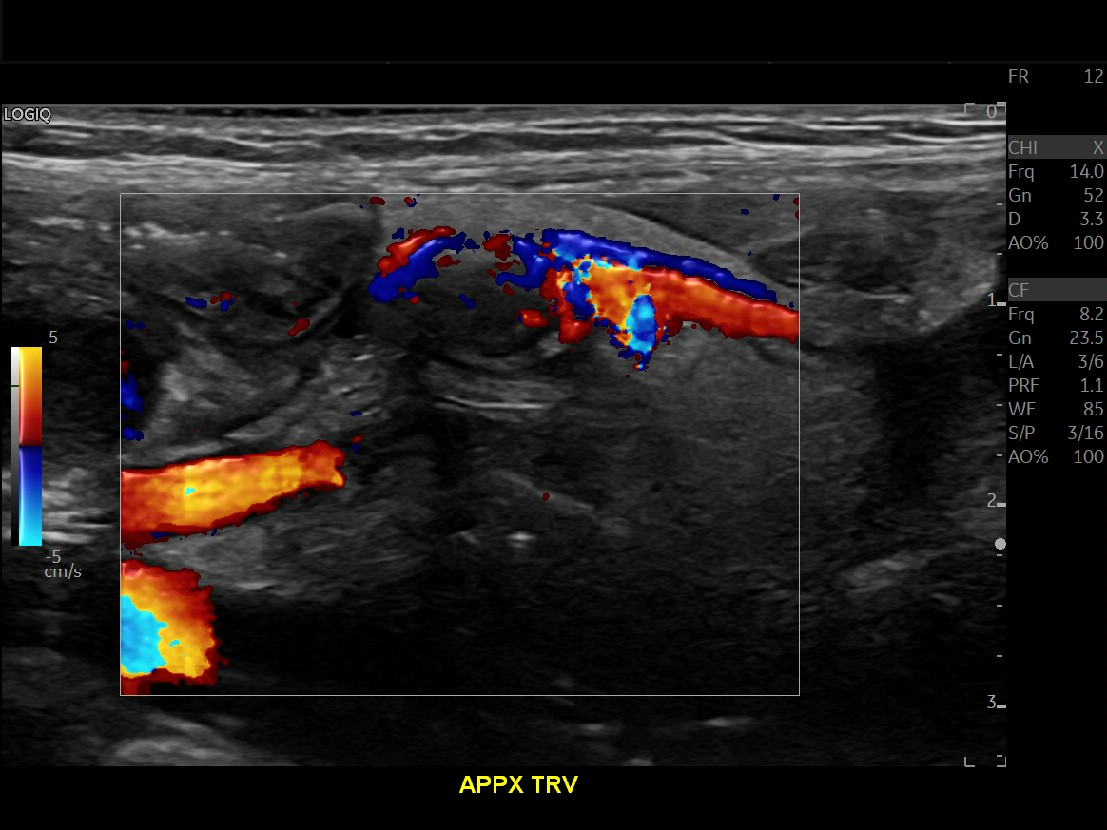

Appendicitis 14

Large appendicitis with appendicolith, hyperemia, fat standing and lympadenitis.